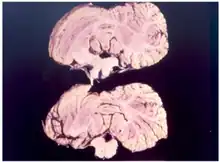

| Diagnostic method | Autopsy |

Kuru is diagnosed by reviewing the patient's history of cerebellar signs and symptoms, performing neurological exams, and excluding other neurological diseases during exams.[15] The symptoms evaluated are typically coordination issues and involuntary muscle movements, but these markers can be confused with other diseases that affect the nervous and muscle system; physical scans are often required to differentiate Kuru from other disorders.[26][27] There is no laboratory test to determine the presence of Kuru, except for postmortem evaluation of central nervous system (CNS) tissues, so diagnoses are achieved by eliminating other possible disorders.